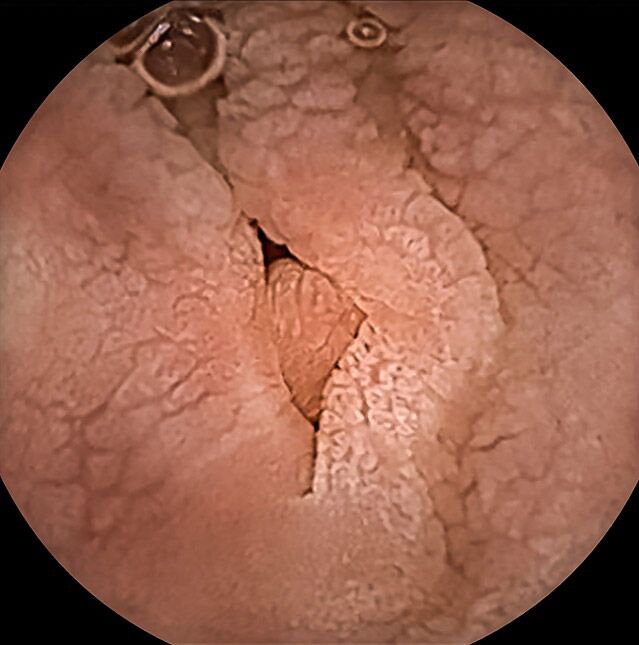

Die verwendete Videokapsel „Kamerapille“ ist eine winzige Digitalkamera, die einschließlich Licht-, Batterie- und Funktechnik nur etwa die Größe eines Gummibärchens hat. Auf ihrem Weg durch den Magen-Darm-Kanal nimmt die Kapsel automatisiert Bilder der Schleimhaut des Verdauungstraktes auf und sendet sie nach außen an einen tragbaren Datenrekorder. Die von uns verwendete neueste Kapselgeneration passt sogar die Bildfrequenz der Geschwindigkeit an, mit der sich die Kamerakapsel im Darm bewegt und kann kleinste Objekte bis zu einer Größe von 0,7 mm erkennen.